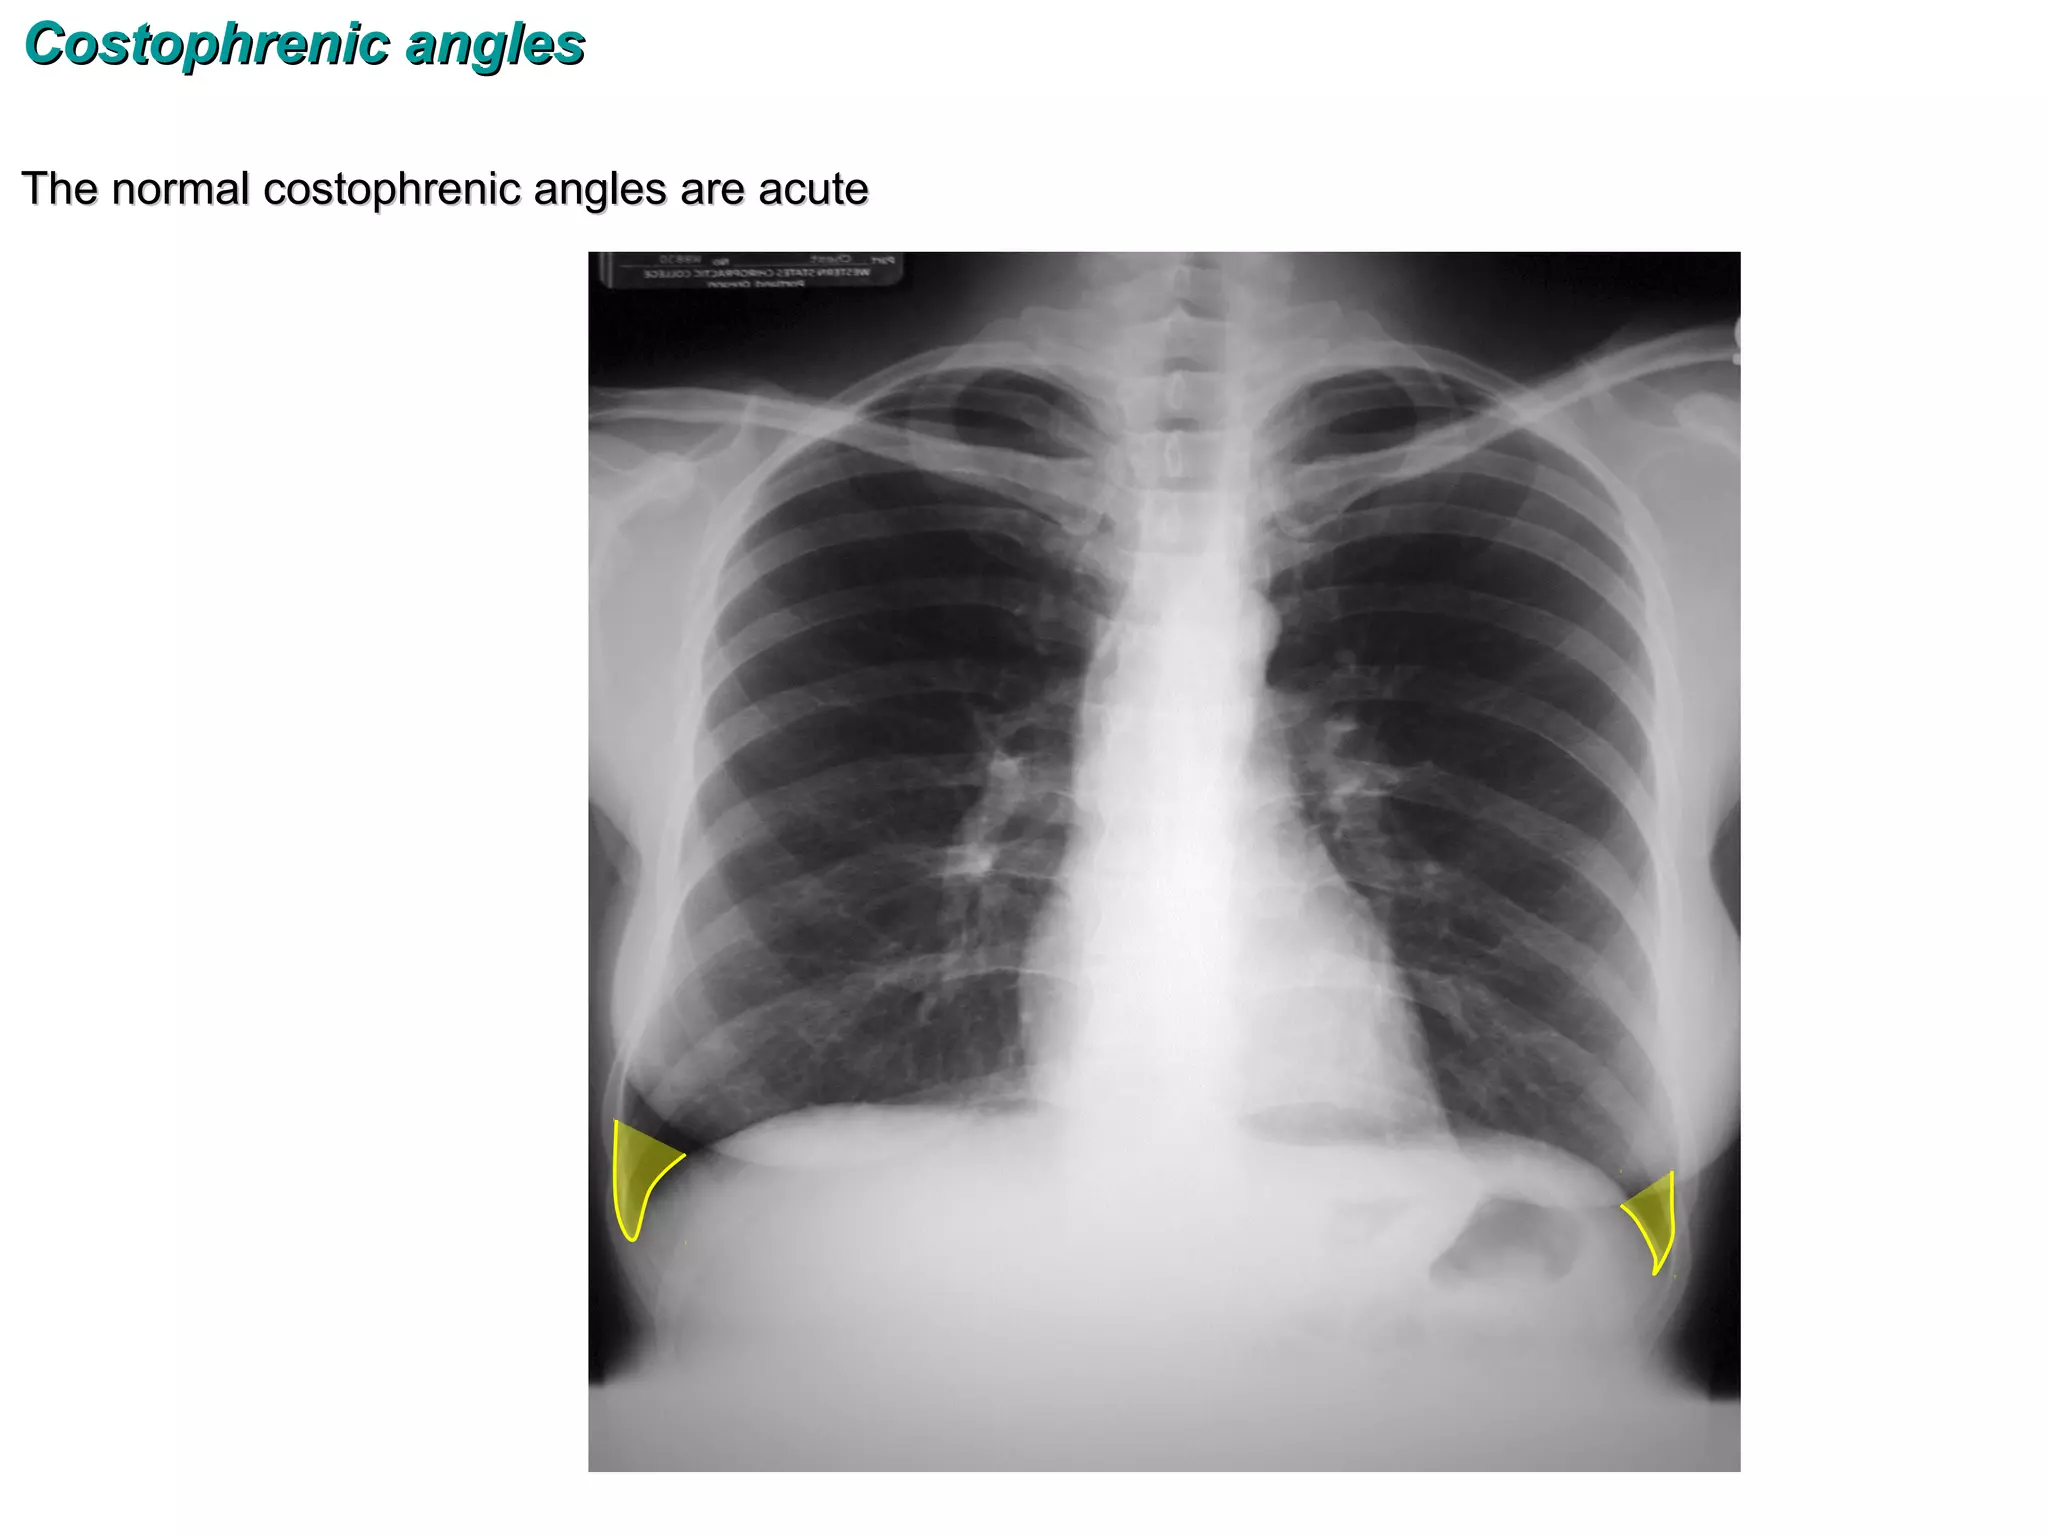

Costophrenic angles

The normal costophrenic angles are acute

Costophrenic angles The normalcostophrenic angles are acute